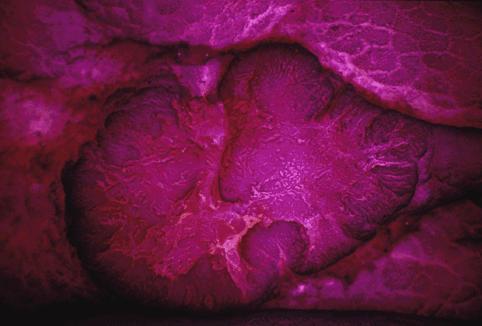

疾病(病理主体)的分类恶性上皮性肿瘤/腺癌

部位(按器官分)大肠/乙状结肠

检查方法切除标本(宏观)

肿瘤的肉眼分类0型(表在型)/IIa型(IIa+IIc)

肿瘤最大直径15~19

肿瘤的深度sm